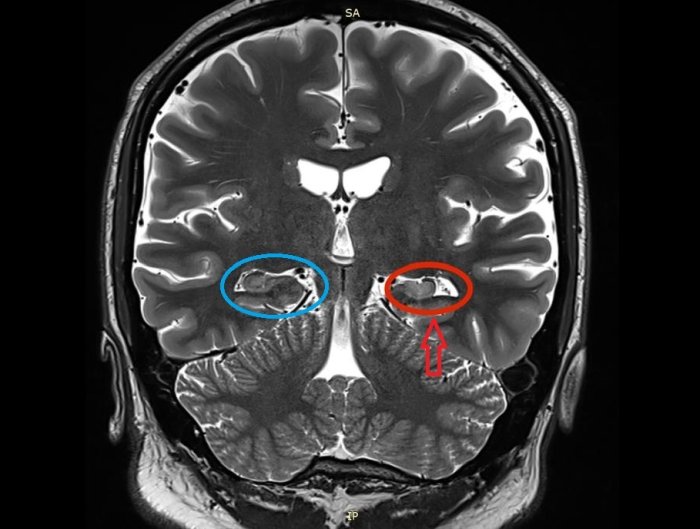

Sclerosi dell'ippocampo sinistro visibile alla risonanza magnetica (Fonte: Uhomachinky/Wikipedia)

L'ippocampo è incorporato in profondità nel lobo temporale del cervello e ha un ruolo importante nell'apprendimento e nella memoria, oltre ad essere influenzato da vari disturbi neurologici e psichiatrici. Tuttavia, i cambiamenti patologici dell'HS-aging di solito si estendono oltre l'ippocampo.

Considerando che il deterioramento della memoria è grave sia nell'HS-aging che nel MA, altre aree come l'elaborazione visuo-spaziale e la funzione esecutiva rimangono piuttosto inalterate nella maggior parte dei casi di HS-aging, poiché l'atrofia associata all'HS-aging è altamente localizzata nell'ippocampo e nelle strutture vicine del cervello.